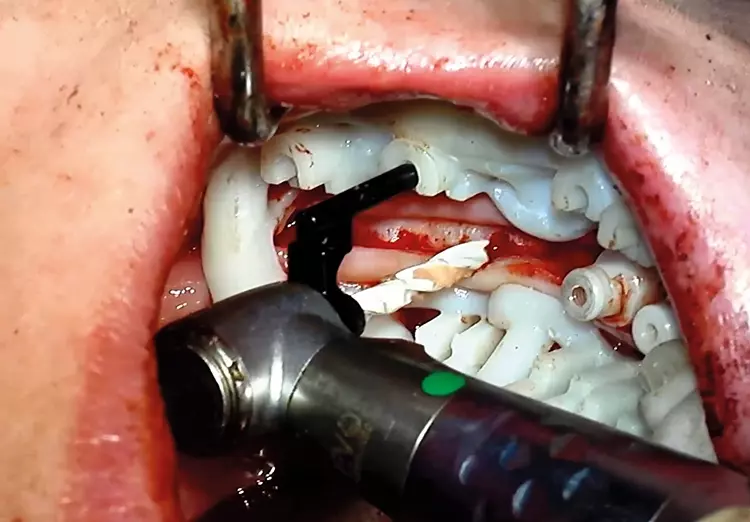

Abb. 10: Die Implantatbohrung und -insertion am Beispiel des 3. Quadranten:

Das Schienensystem SDS BOX FULL NAVIGATION SYSTEM ermöglicht mit den lateralen

Führungshülsen bei ausreichender Wasserkühlung eine uneingeschränkte

Sicht auf das Insertionsgebiet, ohne metallischen Abrieb für das eröffnete Knochenlager

in Kauf zu nehmen. SDS

Abb. 10: Die Implantatbohrung und -insertion am Beispiel des 3. Quadranten: Das Schienensystem SDS BOX FULL NAVIGATION SYSTEM ermöglicht mit den lateralen Führungshülsen bei ausreichender Wasserkühlung eine uneingeschränkte Sicht auf das Insertionsgebiet, ohne metallischen Abrieb für das eröffnete Knochenlager in Kauf zu nehmen.

Stattdessen treten an die Stelle von Bohrhülsen zwei laterale Führungshülsen, welche wiederum in zwei Führungsarmen befestigt unmittelbar mit dem Winkelstück verbunden sind und direkten Blick auf das OP-Gebiet sowie eine sehr präzise Insertion des Implantates erlauben (Abb. 10-12). Dies gewährleistet die Implantation ohne partikuläre Verunreinigungen, weshalb das SDS System bisher als einziges Navigationssystem weltweit mit dem „Approved by CleanImplant“-Siegel zertifiziert wurde. Es kann jedes Zubehör, das über einen ISO-Adapter in ein Winkelstück passt, mit dem SDS (Navigations-)System verwendet werden.

Die „2ingis“-Schienen wurden beim SDS BOX FULL NAVIGATION SYSTEM effizient an die SDS Keramikimplantate und die weiteren vollkeramischen Bohrkomponenten angepasst. Das Besondere dabei ist, dass das System nicht über eine zentrale metallische Bohrhülse geführt wird, welche zwangsläufig unerwünschten Material-Abrieb bedeutet.